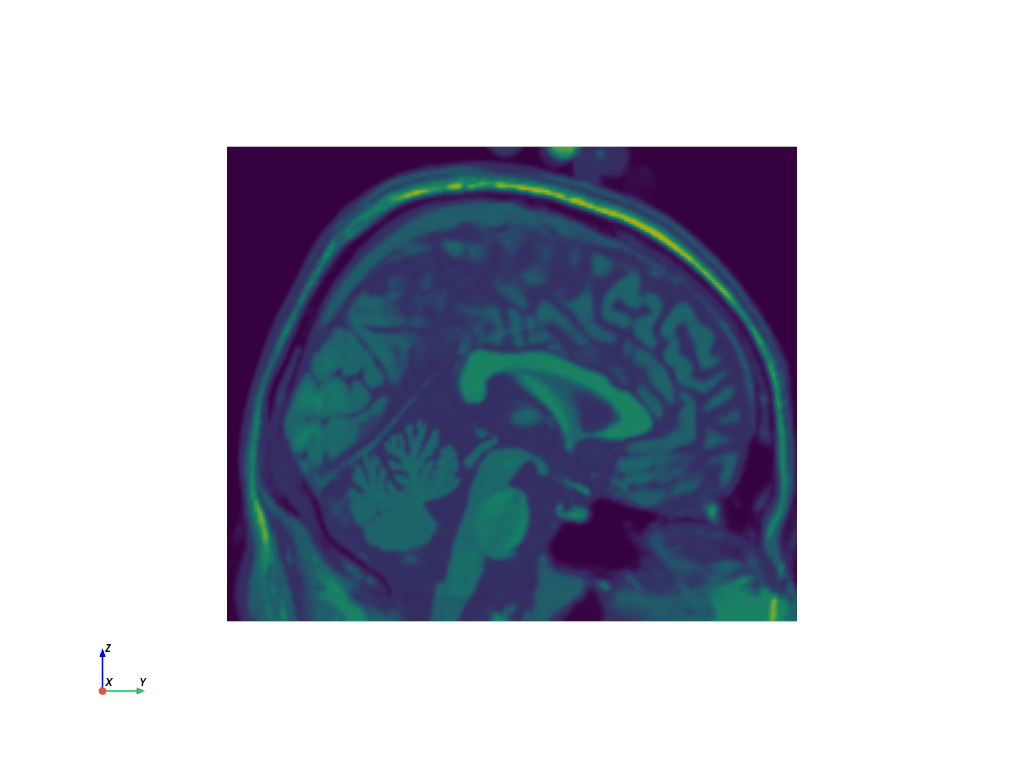

>>> import pyvista >>> from pyvista import examples >>> filename = examples.download_brain(load=False) >>> filename.split("/")[-1] # omit the path 'brain.vtk' >>> reader = pyvista.get_reader(filename) >>> mesh = reader.read() >>> sliced_mesh = mesh.slice('x') >>> sliced_mesh.plot(cpos='yz', show_scalar_bar=False)